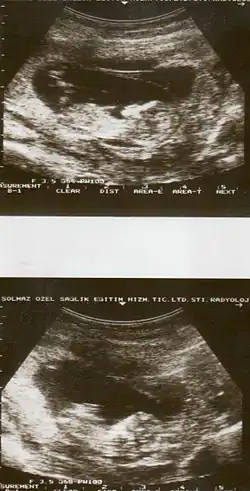

Placental abruption is suspected when a pregnant mother has sudden localized abdominal pain with or without bleeding. The fundus may be monitored because a rising fundus can indicate bleeding. An ultrasound may be used to rule out placenta praevia but is not diagnostic for abruption.[8] The diagnosis is one of exclusion, meaning other possible sources of vaginal bleeding or abdominal pain have to be ruled out in order to diagnose placental abruption.[5] Of note, use of magnetic resonance imaging has been found to be highly sensitive in depicting placental abruption, and may be considered if no ultrasound evidence of placental abruption is present, especially if the diagnosis of placental abruption would change management.[16]